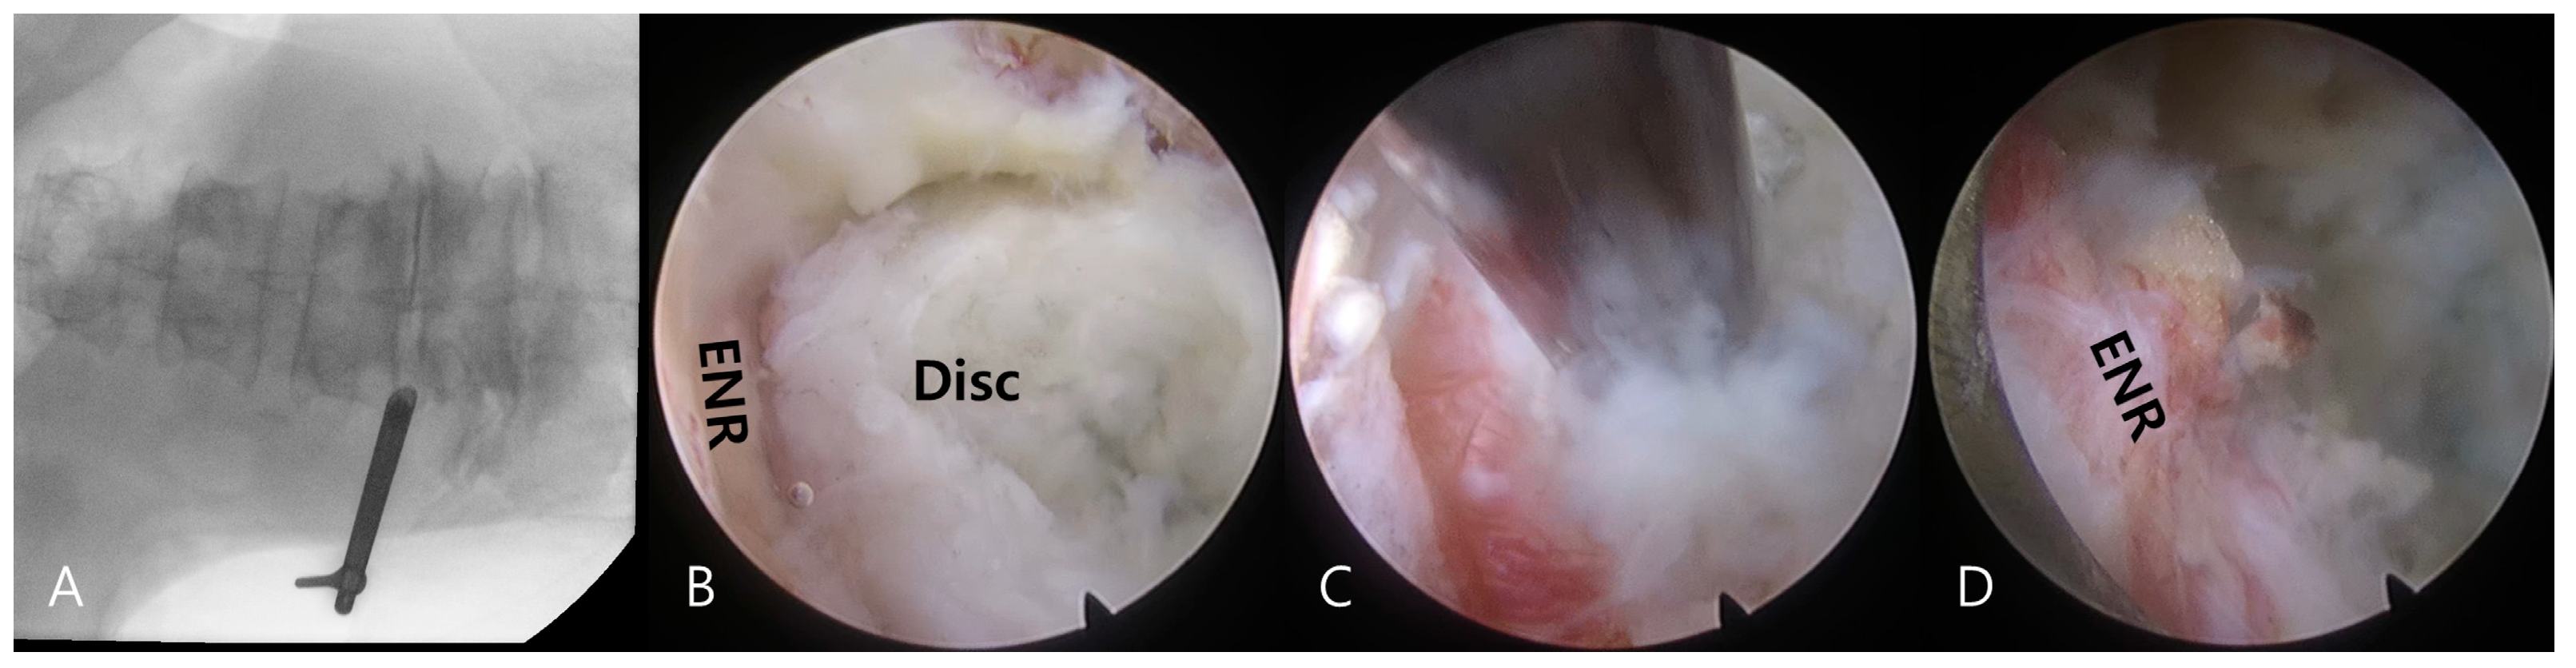

2.3. Surgical Technique